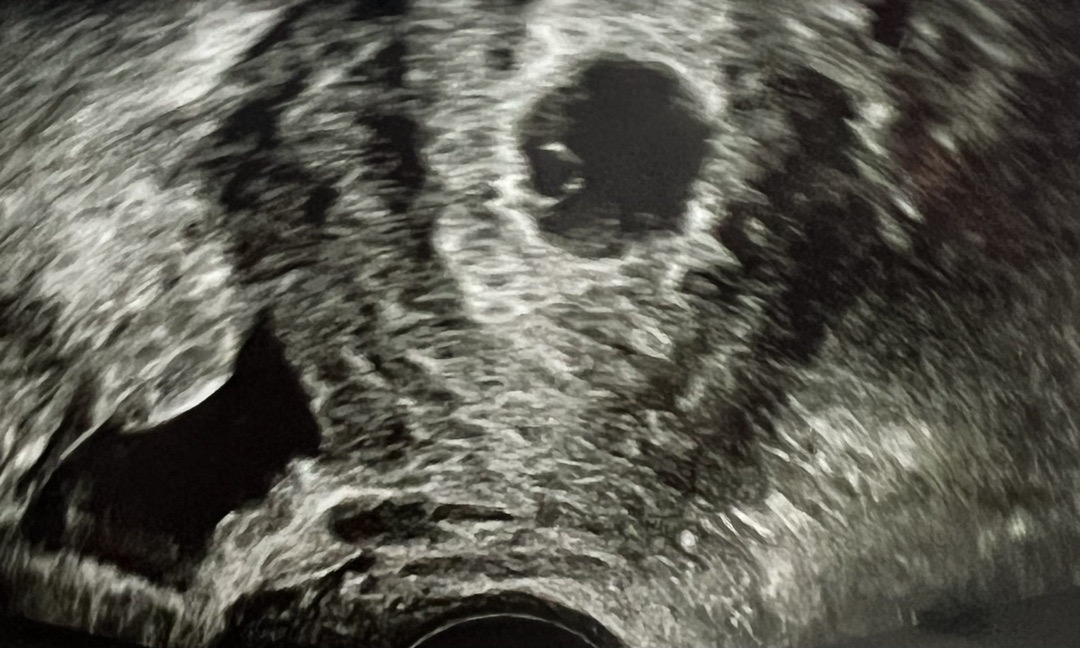

월요일엔 갈색혈이 조금 비치다가 화요일에 갈색혈이 왈칵 나와서 병원에 갔다왔었는데 피고임도 없고 깨끗했어요. 그렇게 아기집 보고왔어요ㅎㅎ 어제는 저녁에 갑자기 새빨간 피가 두 패드는 적시길래 잘못된줄알고 오늘 바로 병원갔는데 피고임 살짝 있는데 괜찮다고 하셨고 아기집이랑 난황도 잘보고 왔거든요. 유산방지 주사도 맞았는데 조금 전 또 새빨간 피가 ㅠㅠ 지금 5주5일차고 둘찐데 첫째랑 넘 달라서 걱정되네요.. 저처럼 피가 나오시는 분 계신가여..